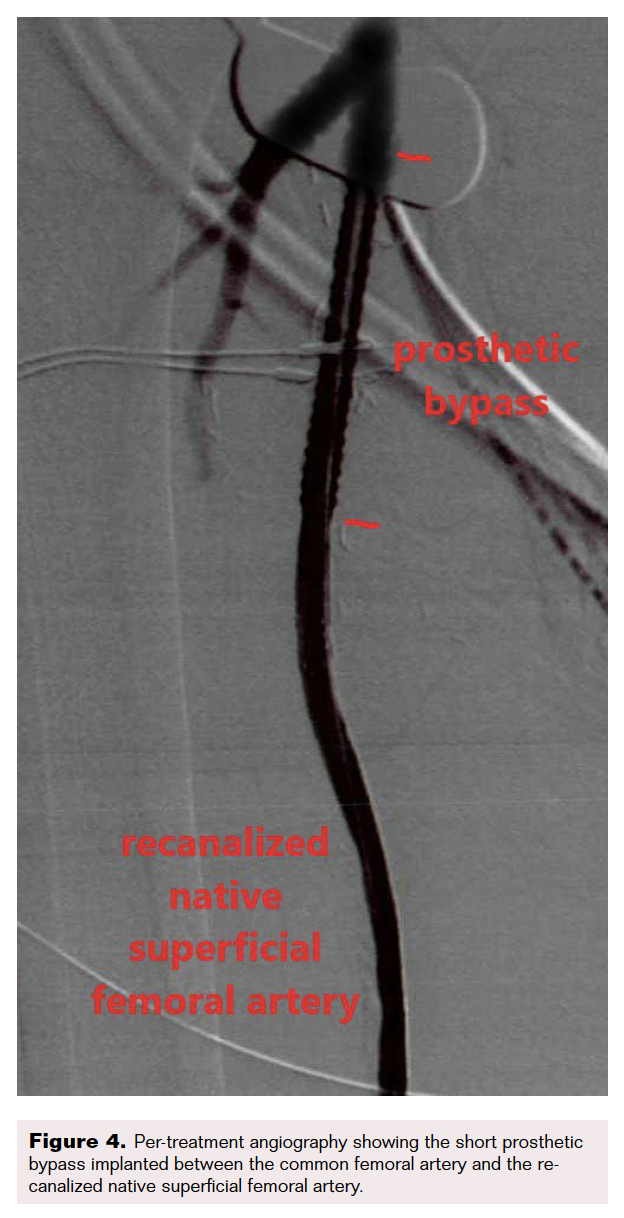

Computed tomography angiography highlighted thrombosis of the femoroposterior tibial bypass and a grade 4 Global Limb Anatomic Staging System femoropopliteal and tibioperoneal trunk chronic total occlusion (CTO). Runoff vessels were patent (Figure 2). Through retrograde posterior tibial puncture, we tried to recanalize the CTO but were not able to get into the common femoral artery (CFA) because the SFA ostium was ligated (Figure 3). We performed a short Dacron prosthetic bypass between the CFA and the proximal part of the SFA (Figure 4), followed by stenting of the whole SFA and the proximal third of the popliteal artery with drug-eluting stents. The distal part of the popliteal artery and the tibioperoneal trunk were treated with balloon angioplasty.